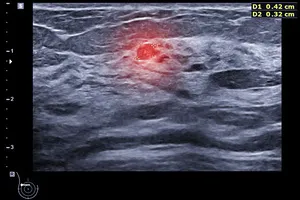

유방암은 암세포가 유방 조직에서 발생하여 주변 조직이나 림프절, 다른 장기로 퍼져나가는 질환입니다. 유방암의 진행 정도를 나타내는 단계를 병기라고 하는데, 유방암 2기는 종양의 크기와 림프절 전이 여부에 따라 세분화됩니다. 일반적으로 종양의 크기가 2~5cm이고 림프절 전이가 일부 있는 경우를 말합니다.

· 유방암 2A기

종양이 2cm 미만이거나 2~5cm 사이이지만 림프절 전이가 없는 경우

· 유방암 2B기

종양이 2~5cm 사이이고 림프절 전이가 있거나, 종양이 5cm 이상이지만 림프절 전이가 없는 경우